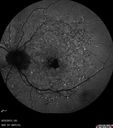

65 year old woman with gradually declining central vision. VA 20/200 in both eyes in the later photos (left eye was better in earlier photos). FAF shows pisciform tri-radiate lesions that are hyper FAF typical of stargardt's fundus flavimaculatus

Stargardt's Macular Dystrophy ABCA4 positivevaatamisi: 536 Fundus Autofluorescence shows central atrophy with Hyper FAF pisciform triradiate lesions. Images show some progression over 3 years of macular dystrophy.00000